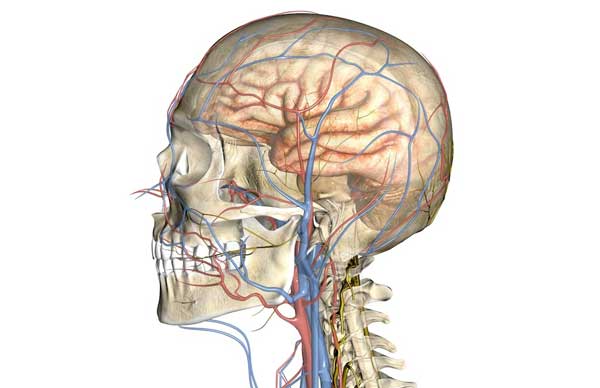

Церебральная ангиодистония

Церебральная форма патологии, как видно из названия, затрагивает сосуды головного мозга. Признаки, указывающие на проблемы с мозговым кровообращением, могут включать:

Часто ангиодистония сосудов головного мозга обусловлена не только сопутствующими заболеваниями, но и образом жизни. Это важно учитывать для достижения положительного результата лечения.

Кровообращение в мозге может ухудшаться из-за предпочтения высококалорийной и жирной пищи, курения и употребления алкоголя. Порой простое изменение рациона на более здоровый может значительно облегчить симптомы нарушенного мозгового кровоснабжения.

Согласно статистическим данным, церебральная ангиодистония является одной из главных причин головных болей у людей молодого и среднего возраста.